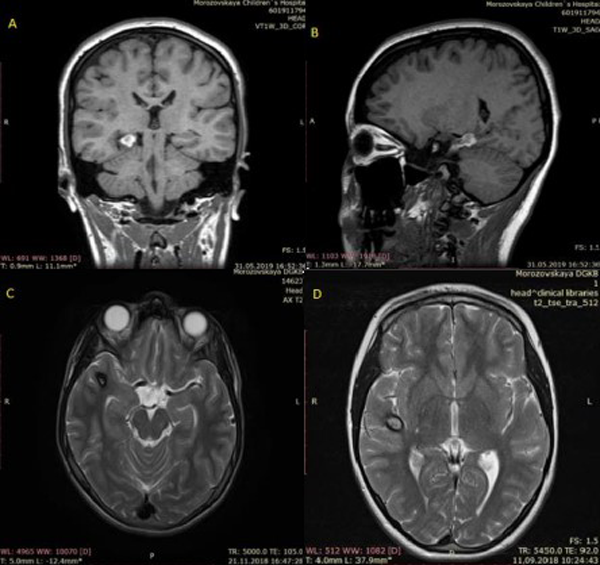

La RM puede identificar lesiones del lóbulo temporal y otras anomalías con una sensibilidad y especificidad de alrededor del 90%. Una amplificación anormal relativa de la señal en la materia gris/blanca del lóbulo temporal, atrofia del fórnix ipsilateral, dilatación del cuerno temporal del ventrículo lateral y desdibujamiento de los límites entre la materia gris y blanca del neocórtex temporal son todos criterios diagnósticos significativos de RM a tener en cuenta. La esclerosis hipocampal del lado derecho se muestra en las Figuras 1A y 1B, y una malformación cavernosa del lóbulo temporal se ve en las Figuras 1C y 1D. Se utilizaron los siguientes procedimientos no invasivos en esta muestra para evaluar a los pacientes antes de la cirugía: RM de 1.5 y 3T, monitoreo de EEG nocturno con video, examen físico neurológico y evaluación semiología. Una vez localizada el área epiléptica, la extensión de la resección quirúrgica fue determinada por electrocorticografía intraoperatoria (ECoG). Además, preoperatoriamente, los pacientes pediátricos se sometieron a evaluaciones neuropsicológicas que incluyeron pruebas estandarizadas adecuadas para la edad para evaluar la cognición, el lenguaje, la memoria, la atención, la resolución de problemas, el análisis visual, espacial, perceptual, habilidades académicas, funciones motoras y sensoriales, comportamiento, personalidad, estado emocional y funcionamiento adaptativo. Se presume el área de disfunción preexistente basada en los datos recopilados, se establece la lateralización de la zona del habla y se evalúan los riesgos y beneficios de la cirugía.4

Figura 1. Esclerosis hipocampal derecha mostrada en las Figuras A y B; y malformación cavernosa del lóbulo temporal en las Figuras 1C y 1D.